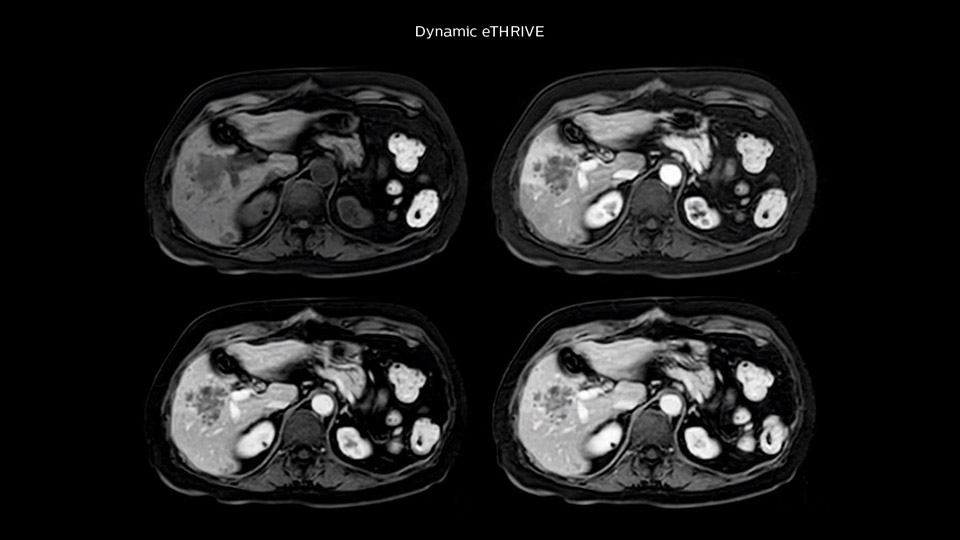

Comparison of liver MRI with and without MultiVane XD motion correction

In this example the image quality of the MultiVane XD images is evidently better than in the images without MultiVane XD. Ingenia 1.5T with dS Torso coil solution.

“We acquire one transversal high resolution T2-weighted sequence with 3 mm slice thickness, for example for pancreas or liver lesions. Then we also add a T2 fat suppressed MultiVane XD SPIR sequence. We perform these two routinely in our liver imaging. We use high dS SENSE factors to significantly shorten scan times to 2-4 minutes, which can improve our protocol; it’s a very robust scan.”

“We include mDIXON for the dynamic sequences because of the robust and homogeneous fat suppression we get with that. We had been using eTHRIVE, but we are now quite happy with mDIXON. Sometimes we use a medication to calm the bowels, to further improve the image quality.”